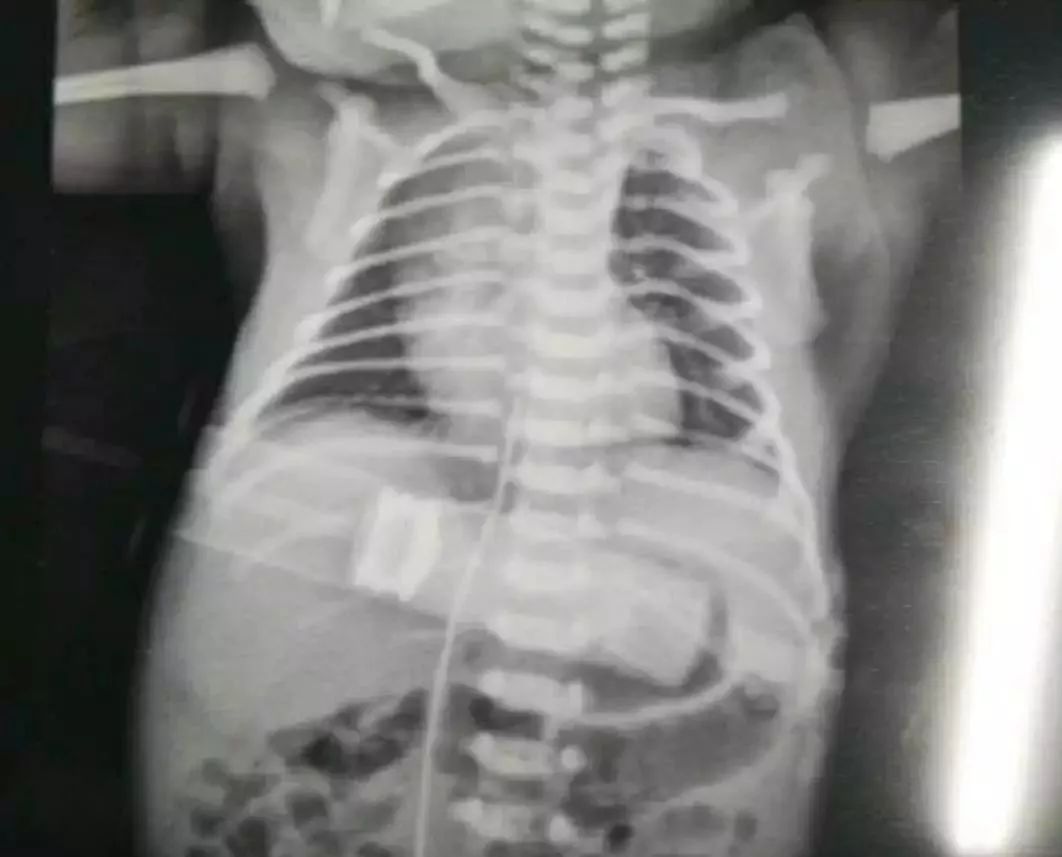

新生儿及胎儿自然通畅的脐静脉是通向人体门静脉系统的奇妙途径。出生后3~5天内静脉导管尚未闭合,经脐静脉插管可进入下腔静脉,形成有效的中心静脉置管。

脐静脉插管可在新生儿生后即可应用,并可保留7~10天,使用方便。临床上用于新生儿窒息复苏、肠外静脉营养、药物、血液和血液制品输注、换血、及中心静脉压监测等,是新生儿尤其是危重新生儿和极(超)低出生体重儿的重要生命通道。